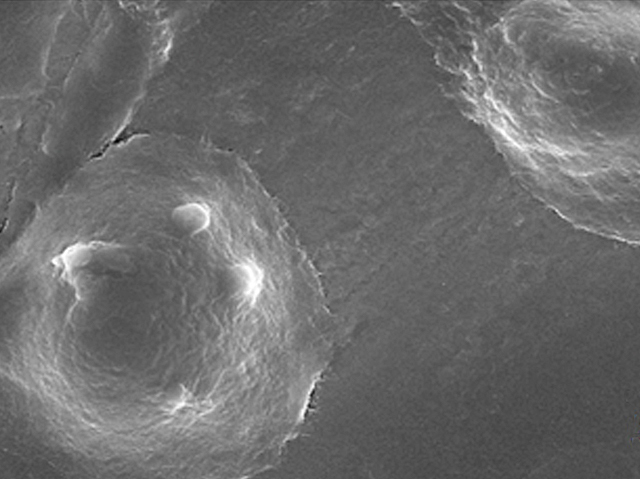

Losing teeth is a distressing experience, whether it’s through injury or disease. Although removable false teeth are a solution, millions of people have had their pearly white smiles restored with dental implants over the past few decades. This involves screwing a titanium fixture into the jaw to replace the root of the missing tooth, which then acts as an anchor for a replacement gnasher. Dentists use titanium because it can bind to the skin cells in the mouth, creating a tight seal for the new tooth. But infections and other gum problems can happen if this seal doesn’t form properly. Scientists have discovered that coating titanium with a naturally-produced chemical called platelet activating peptide attracts skin cells and helps them to settle into their new home. So far this has only been tested with cells grown in the lab, but it will hopefully lead to better implant materials in future.